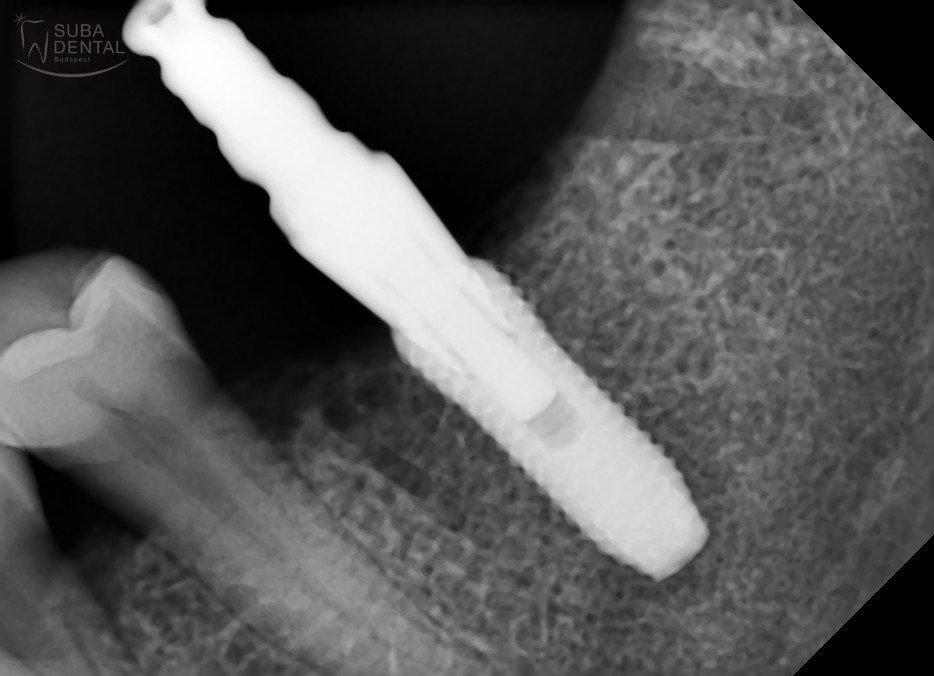

Zárt kanalas lenyomatvételi fejről készült kontroll panorámaröntgen-felvétel a precíziós lenyomatvételt megelőzően